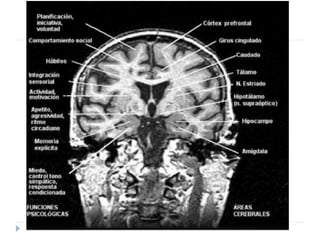

Cambios anatómicos

Hipocampo

• Disminución

de la

sustancia

blanca

Amígdala

• Aumento de

volumen en

personas

medicadas

Corteza

cerebral

• Corteza

orbitofrontal

32% menor

• Reducción

de densidad

glial en

cíngulo

anterior.

Cambios anatómicos Hipocampo • Disminución de la sustancia blanca Amígdala • Aumento de volumen en personas medicadas Corteza cerebral • Corteza orbitofrontal 32% menor • Reducción de densidad glial en cíngulo anterior.